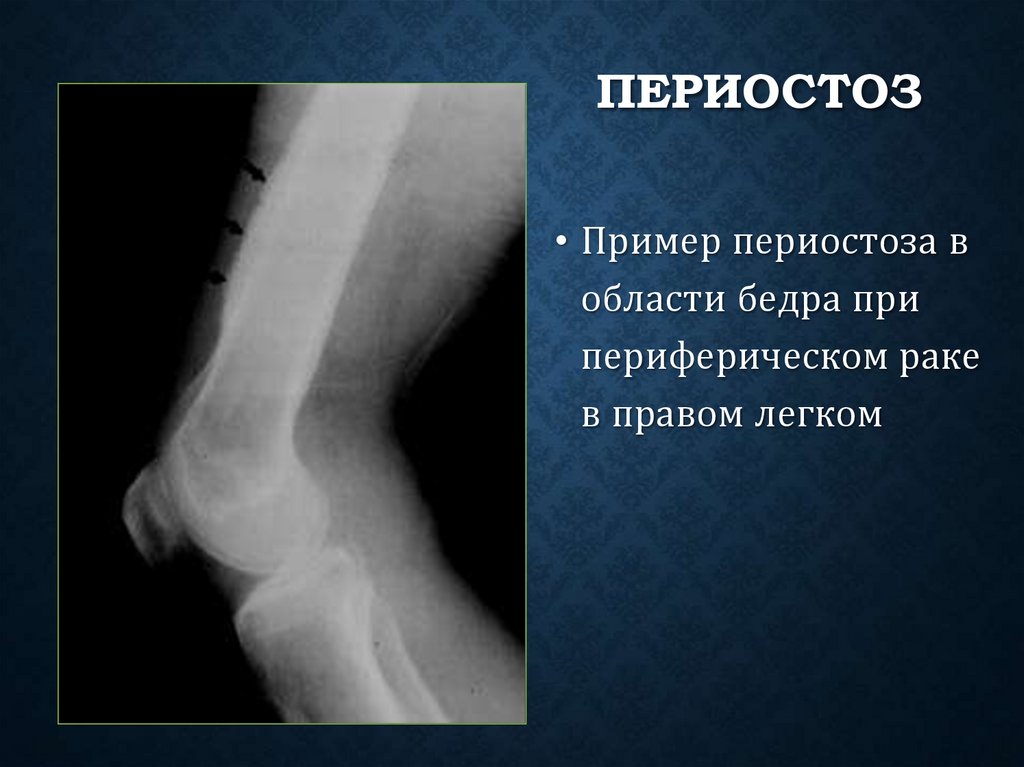

84. Периостоз

ПЕРИОСТОЗ

• Периостоз (periostosis) — периостальное костеобразование,

при котором вокруг диафиза откладываются многочисленные

слои новообразованной костной ткани.

• Причиной периостоза могут быть воспалительные,

травматические, токсические, неопластические и

гормональные изменения.

85. Периостоз

• Пример периостоза в

области бедра при

периферическом раке

в правом легком